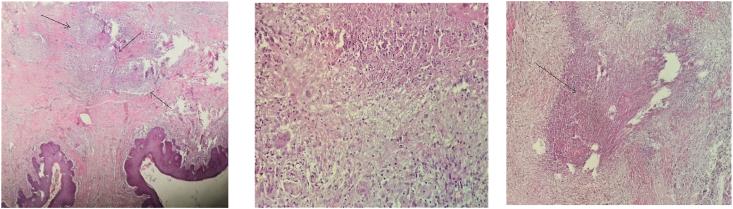

Tuberculosis poses a real public health problem inTunisia.We report an 80-year old patient, immunocompetent, who has initial presentation of a painless ulcerative lesions of the glans penis. A history of pulmonary tuberculosis was not present.The physical examination revealed an indurated glans penis covered with blackish crusts and small ulcerations. A biopsy of the lesion was undertaken and histological examination was confirmed the diagnosis of tuberculosis of glans.Others investigations was performed without finding any abnormalities He responded well to anti-tubercular treatment with complete resolution of lesions in six months.

结核病在突尼斯构成了一个切实的公共卫生问题。我们报告了一名80岁免疫功能正常的患者,其最初表现为阴茎头无痛性溃疡性病变。无肺结核病史。体格检查发现阴茎头硬结,覆盖有黑色痂皮和小溃疡。对病变进行了活检,组织学检查确诊为阴茎头结核。还进行了其他检查,未发现任何异常。他对抗结核治疗反应良好,六个月内病变完全消退。